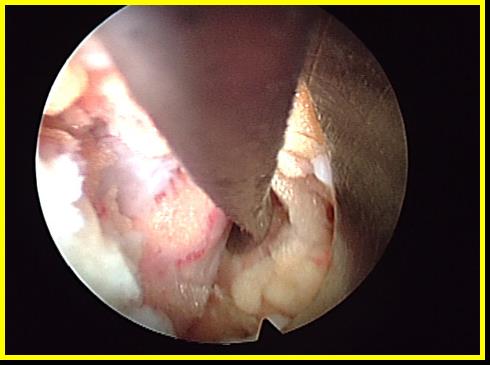

Операция осуществляется через рабочий канал внутри эндоскопа с постоянной подачей жидкости, под визуальным контролем и при использовании сменных инструментов. После того, как открыта желтая связка, можно войти в позвоночный канал. Управление оптикой по принципу джойстика обеспечивает мобильность. Скошенная рабочая используется в качестве второго инструмента, при вращении она может служить защитой невральных структур. Благодаря возможности поворота скошенная рабочая гильза может использоваться как второй инструмент.

Раскрытие желтой связки и работа различными инструментами.

После отведения твердой мозговой оболочки при помощи скошенного конца рабочей гильзы, производится удаление грыжи диска.